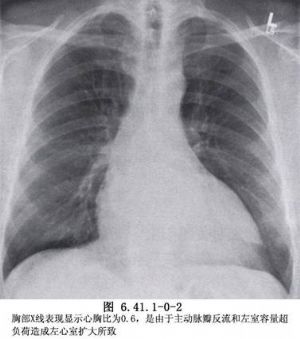

1、有一种比较少见的强直性脊柱炎的征兆就是会出现主动脉瓣关闭不全的现象,不过也只是轻微的现象,到目前为止还没有发现比较严重的主动脉瓣关闭不全的案例,个别的强直性脊柱炎可能会出现非特异性传导阻滞的病变,这些症状也是发生在儿童身上的,相对来说是非常的少见的。